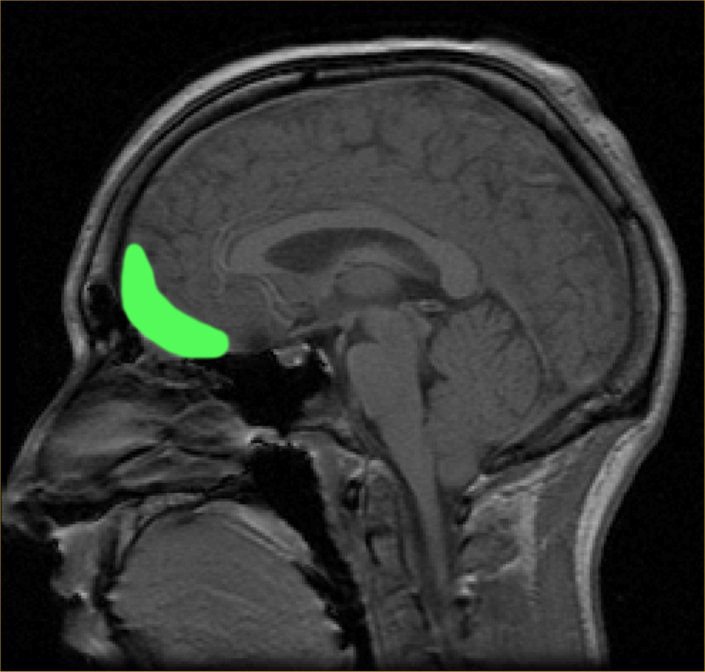

Speaking from a physiological perspective, dance’s music is known to stimulate the orbitofrontal cortex of the brain, which is located right behind the eyes. The orbitofrontal cortex is the major reward and pleasure region of the brain. The amount of stimulation caused here is dependent on how much we enjoy a particular tune.